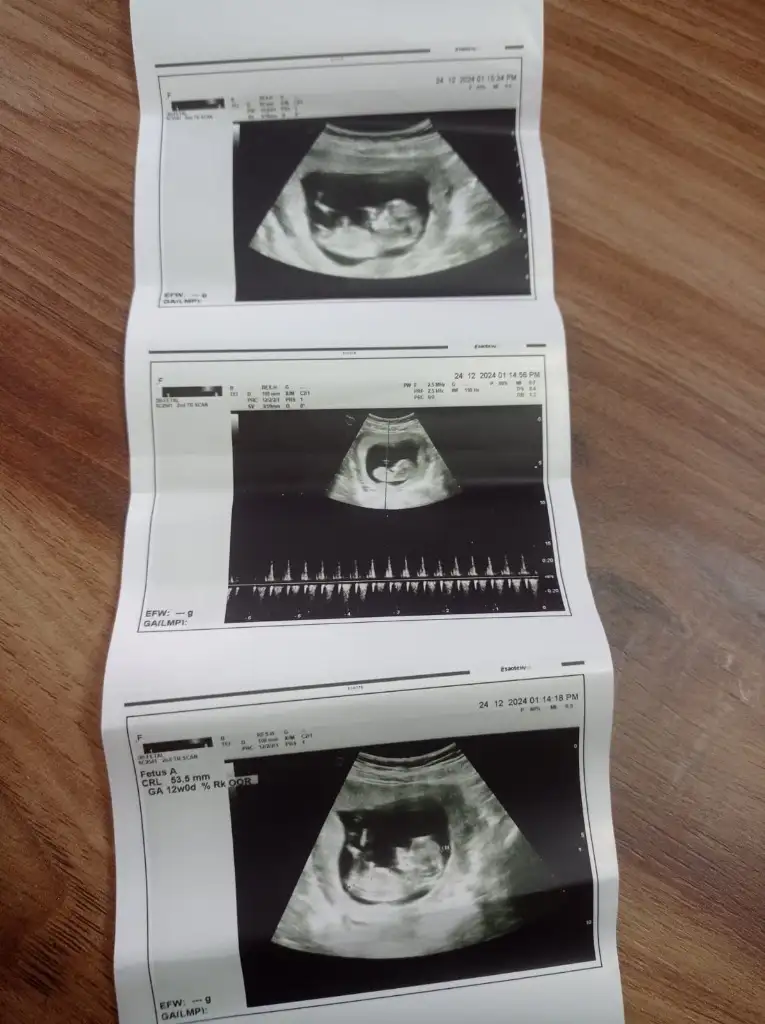

Banada yorum yapabılırmısınızÇok net görünüyor erkek. Hayırlı olsun

Ben bu bebeğin nubunu göremedim ya fotoğraf hiç net değilBanada yorum yapabılırmısınız

Buna yorum yapabılırmısınız pekıBen bu bebeğin nubunu göremedim ya fotoğraf hiç net değil

Burda erkek gibi görünüyorBuna yorum yapabılırmısınız pekı